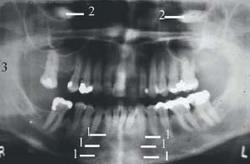

The image on the right demonstrates the dorsal surface of the tongue (1), separated from the hard and soft palates by the palatoglossal air space (2). This space is eliminated by having the patient place the tongue against the palate during exposure.